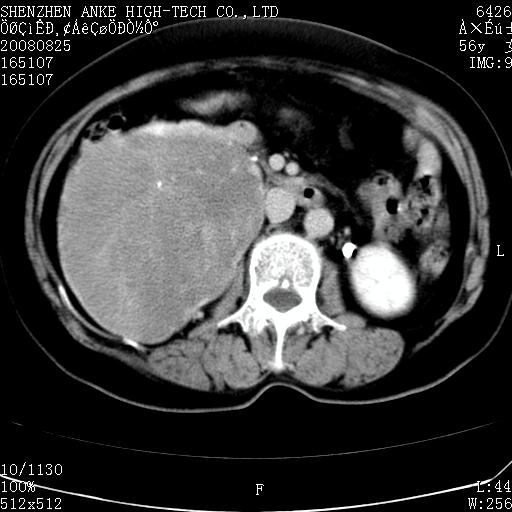

患者,女性,56岁,腰痛3年,查:右腹部约8x10cm肿块,固定,无压痛;8月23日在外院做了平扫,发现右肾巨大肿块(外院具体诊断不祥);今天在我院做了静脉肾盂造影,示:右肾明显增大,分泌功能明显减弱。

1)考虑右肾癌并右肾静脉瘤栓形成。2)脂肪肝。